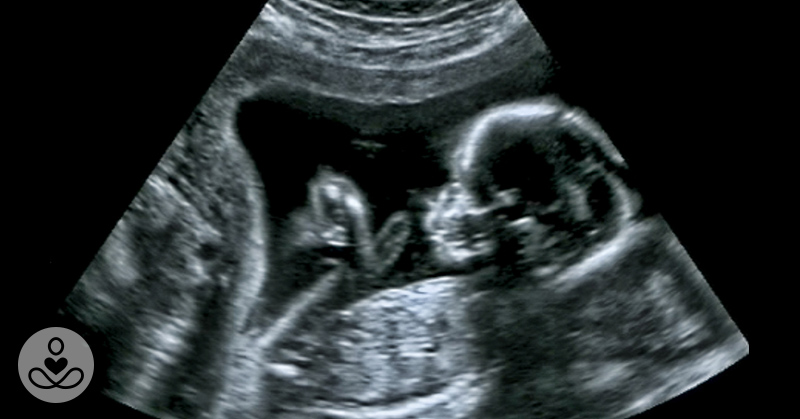

Yet new work is shifting attention backward toward pregnancy, where foundational systems first take shape.

Researchers believe the mother’s microbial world may quietly guide fetal brain development during critical windows.

It suggests a mother’s gut health might shape her child’s neurological future even before birth.